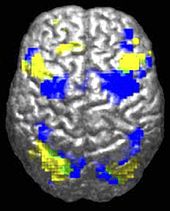

Research into causes has been hampered by the inability to identify biologically meaningful subgroups within the autistic population and by the traditional boundaries between the disciplines of psychiatry, psychology, neurology and pediatrics. Newer technologies such as fMRI and diffusion tensor imaging can help identify biologically relevant phenotypes (observable traits) that can be viewed on brain scans, to help further neurogenetic studies of autism; one example is lowered activity in the fusiform face area of the brain, which is associated with impaired perception of people versus objects. It has been proposed to classify autism using genetics as well as behaviour.

ASD-related patterns of low function and aberrant activation in the brain differ depending on whether the brain is doing social or nonsocial tasks. In autism there is evidence for reduced functional connectivity of the default network, a large-scale brain network involved in social and emotional processing, with intact connectivity of the task-positive network, used in sustained attention and goal-directed thinking. In people with autism the two networks are not negatively correlated in time, suggesting an imbalance in toggling between the two networks, possibly reflecting a disturbance of self-referential thought. A 2008 brain-imaging study found a specific pattern of signals in the cingulate cortex which differs in individuals with ASD.

The underconnectivity theory of autism hypothesizes that autism is marked by underfunctioning high-level neural connections and synchronization, along with an excess of low-level processes. Evidence for this theory has been found in functional neuroimaging studies on autistic individuals and by a brainwave study that suggested that adults with ASD have local overconnectivity in the cortex and weak functional connections between the frontal lobe and the rest of the cortex. Other evidence suggests the underconnectivity is mainly within each hemisphere of the cortex and that autism is a disorder of the association cortex.